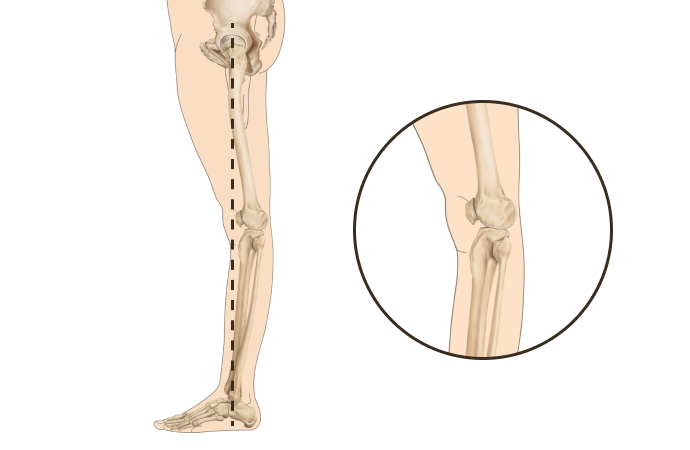

X다리

• 무릎이 안쪽으로 모이면서 다리 축이 변형됨

• 체중 부하가 다리 바깥쪽에 집중되어 외측 관절의 압력증가로

무릎 통증, 불안정성, 관절 손상을 유발할 수 있음

• 허벅지 바깥쪽 근육이 과도하게 발달하고 안쪽 근육이 약화되면 외반슬이 진행

휜다리는 단순히 무릎 사이 간격이 벌어진 것이 아닙니다.

무릎 위의 대퇴골과 아래의 정강이뼈가 회전하면서 무릎까지 뒤로 빠지기 때문에 다리사이 간격이 넓어지는 겁니다.

당당 휜다리

발(아치)-발목-무릎관절-고관절-골반의 서로 다른 회전을 바로 잡는 기술입니다.